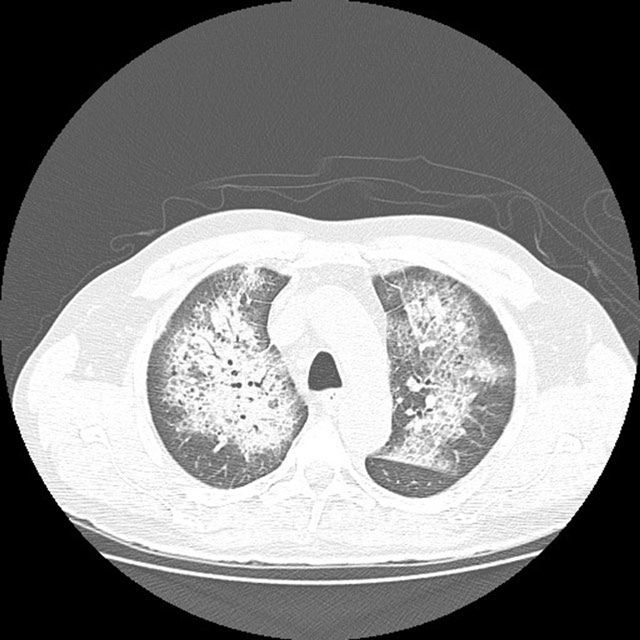

30. A 48 years female presented with weight loss, and nausea for 2 months.

She had a history of exertional dyspnea, dry cough off and on and antitubercular treatment 2 years ago.

She also had history of low backache . She admits to polyuria and polydipsia.

Her laboratory findings showed :

a Serum alkaline phosphatase 918 IU/L (raised)

serum total calcium 14.6mg/dl (raised)

serum phosphate 4.1mg/dl , urea 63.5 mg/dl

creatinine 3.8 mg/dl

serum Na + 141.3meq/L, K + 4meq/L

24 hour urinary calcium 990 mg/day

serum iPTH- 14.3pg/ml ( reference value 15-65)

Serum angiotensin converting enzyme (SACE) level was 158 U/L (Reference value 8- 65).

QTc interval in electrocardiogram was 0.40sec. Ultrasound of the abdomen showed hepatosplenomegaly.

Her CT thorax is shown below

Image description

What is the most likely diagnosis?